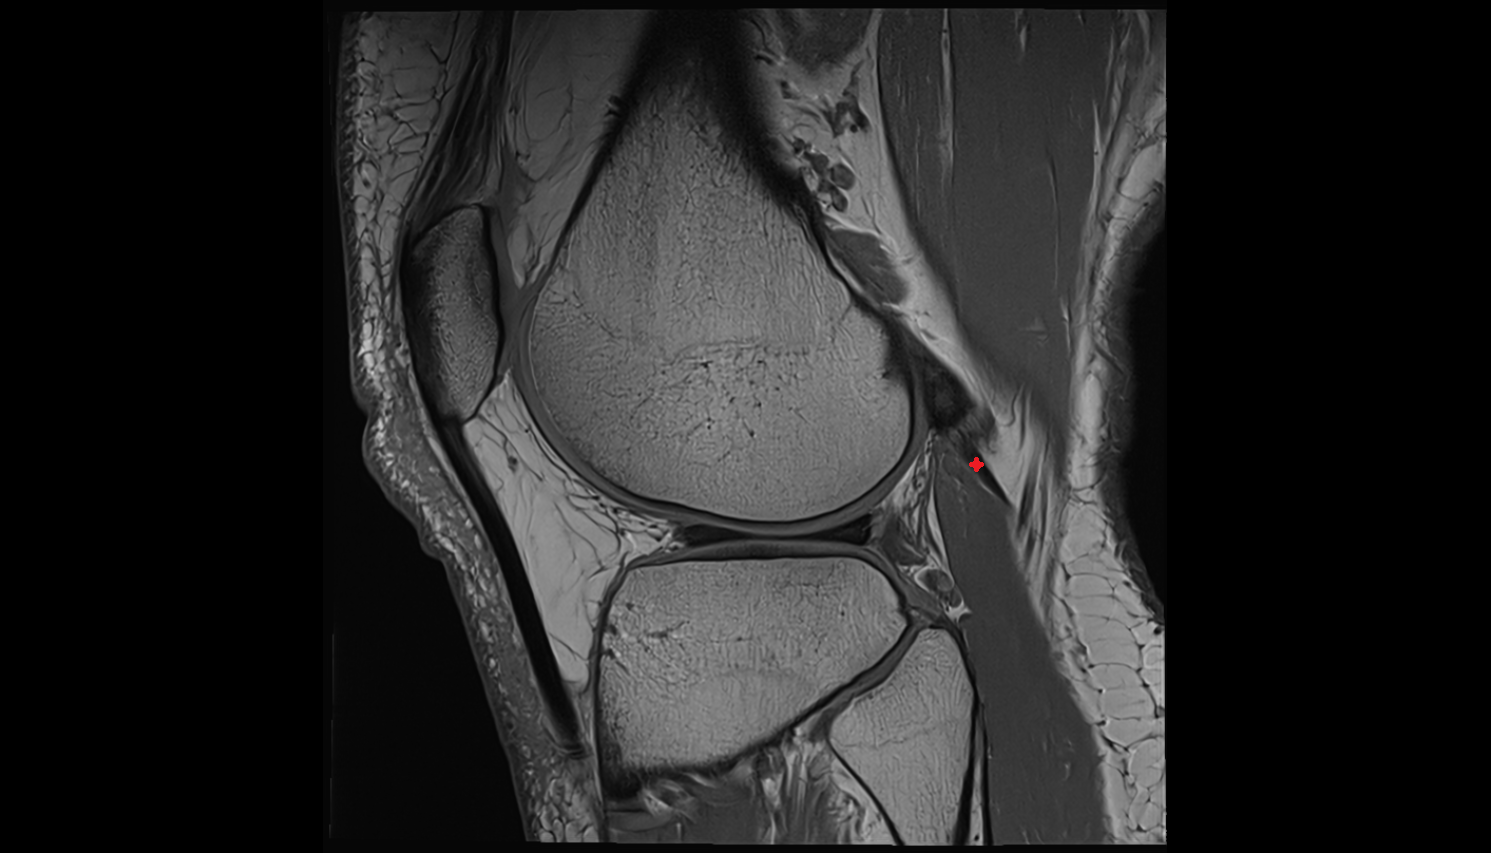

- Anterior cruciate ligament

- Posterior cruciate ligament

- Anterolateral ligament of knee

- Medial meniscus

- Lateral meniscus

- Knee Joint